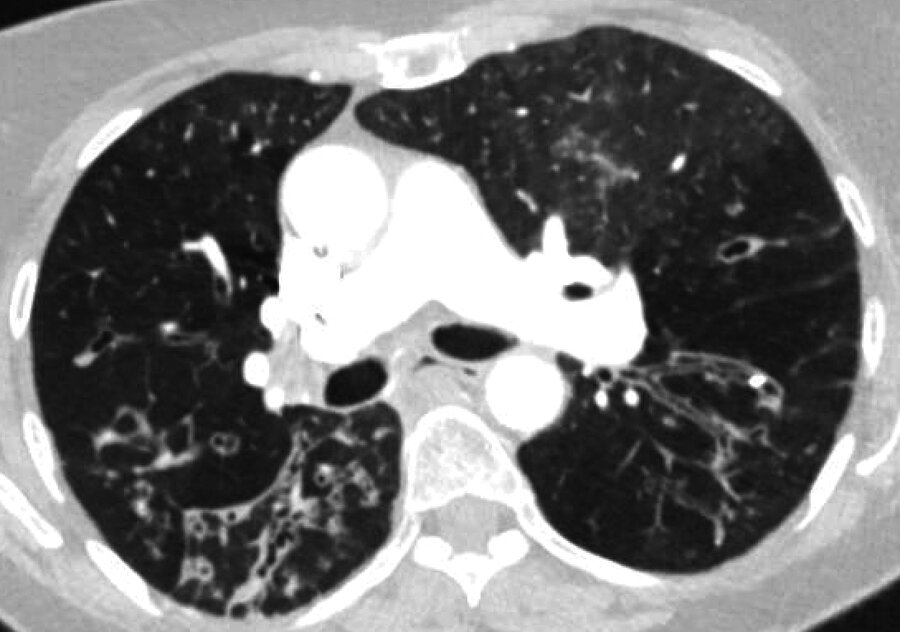

Most likely diagnosis:

1) Disseminated histoplasmosis

2) Rheumatoid Nodules

3) Microscopic Polyangiitis

4) Miliary Tuberculosis

Rheumatoid Nodules